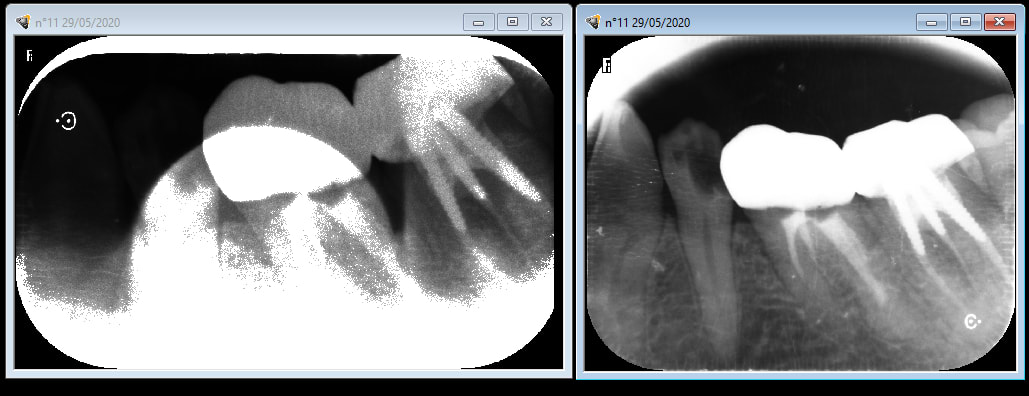

bon je crois que je suis poursuivi par la malédiction du rayon X

en ce moment je prends une radio , je la mets dans le carestream CS 7200 , la radio apparait elle est mimi , ça dure 1/2 seconde et piouff toute pourrie .

PS : sans changer les réglages très souvent la 2 eme ou la 3 eme ça va à peu près .

j en peux plus , sais plus quoi faire . j ai même arraché une dent neuve croyant voir une enooorme carie , ça va que c était une 8 du bas .

belle couleur , certes , mais tjs des radios pourries .